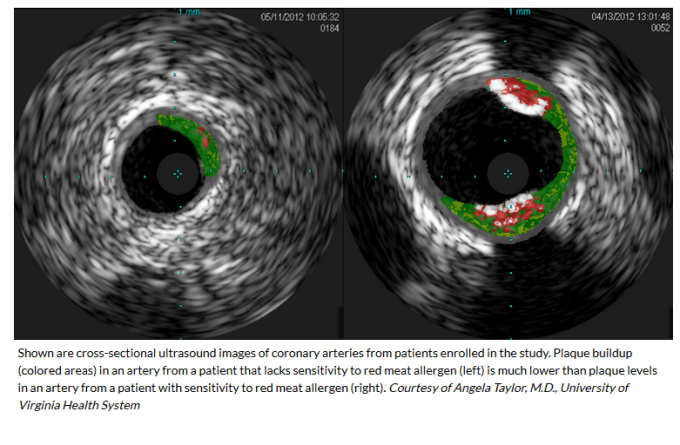

28% people show antibodies to it and that subgroup have 30% more arteriosclerosis:

- “118 subjects who presented for cardiac catheterization and underwent intravascular ultrasound”

- IgE to α-Gal (red meat) was detected in 26%

- “quantity of plaque was 30 percent higher in the alpha-Gal sensitized patients than in the non-sensitized patient” – as quoted from:

NIH-supported researchers find link between allergen in red meat and heart disease

https://www.nhlbi.nih.gov/news/2018/nih-supported-researchers-find-link-between-allergen-red-meat-and-heart-disease

- “In subjects ≤65 years of age, the strength of the association with atheroma burden was stronger (P<0.001), and plaques in the sensitized group had less stable features based on intravascular ultrasound.”